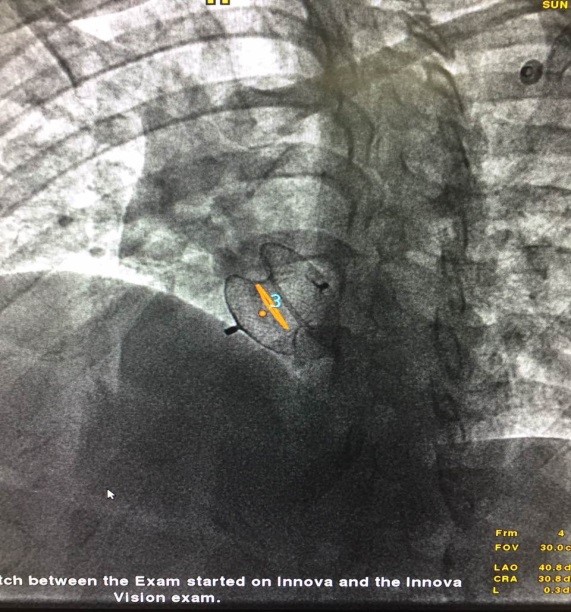

c、规划室间隔缺损位置,为术中实时引导释放封堵器进行标记和提示

(2)术中智能3D实时引导封堵器释放,融合影像与心跳/呼吸同步--可精确引导,降低风险,减少造影剂的用量,缩短手术时间